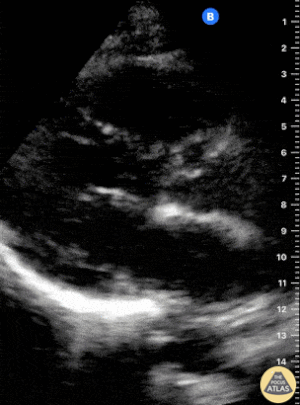

Kısa aks görüntüsünde, pulmoner arter basıncının artmasına bağlı olarak sağ ventrikül genişledikçe interventriküler septum sol kalbe doğru bombeleşir. Bu durum sol ventrikülde D-şekilli görünüm (D-sign) oluşturur.

Apikal dört boşluk görüntüsünde sağ ventrikül normalde sol ventrikülün yaklaşık üçte ikisi büyüklüğünde olmalıdır. Eğer iki ventrikül aynı boyutta görünüyorsa bu durum anormal kabul edilir ve dilatasyon düşündürür.

Bir diğer önemli bulgu McConnell belirtisidir. Bu bulgu, sağ ventrikül serbest duvarında hipokinezi bulunurken apeksin korunmuş olması şeklinde tanımlanır.

Önemli bir hata, sağ ventrikül disfonksiyon bulgularını otomatik olarak akut bir sürece (örneğin pulmoner emboli) bağlamaktır. Yukarıda belirtilen bulgular hem akut hem de kronik durumlarda görülebilir. Bu nedenle klinik bağlam ve hasta öyküsü önemlidir. Önceden yapılmış bir ekokardiyografi raporu, yatak başı değerlendirme ile karşılaştırma yapmak açısından çok yardımcı olabilir.

Apikal dört boşluk görüntüsü alınırken dikkatli olunmalıdır. Eğer görüntü aks dışı alınırsa sağ ventrikül kısalmış (foreshortened) görünebilir ve dilatasyon gözden kaçabilir. Bu hatadan kaçınmak için probu hafifçe döndürerek sağ kalbin en geniş göründüğü düzlemi yakalamak gerekir.